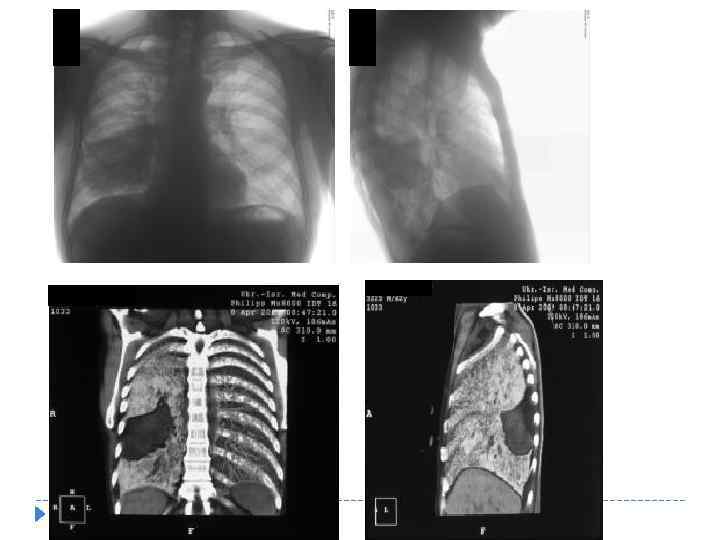

ТУБЕРКУЛЕЗНЫЙ ПЛЕВРИТ (В ТОМ ЧИСЛЕ ЭМПИЕМА) Проявляется воспалением плевры и накоплением экссудата в плевральной полости при отсутствии видимых изменений в легких и ВГЛУ. Для экссудативного плеврита характерны «синдром ограниченного» , «синдром субтотального» и «синдром тотального затемнения» со смещением органов средостения в противоположную сторону.

ТУБЕРКУЛЕЗНЫЙ ПЛЕВРИТ (В ТОМ ЧИСЛЕ ЭМПИЕМА) Проявляется воспалением плевры и накоплением экссудата в плевральной полости при отсутствии видимых изменений в легких и ВГЛУ. Для экссудативного плеврита характерны «синдром ограниченного» , «синдром субтотального» и «синдром тотального затемнения» со смещением органов средостения в противоположную сторону.